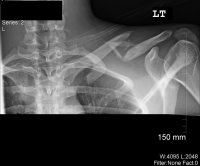

Update: July 22, 2010

Well I saw the doctor today, the first time since surgery, and I got some new x-rays. Good news is that it's healing just fine and have great ROM. The bad news, I can't

for another 2 1/2-3 months.

The reason he gave is that the nature of the break is so bad that if I were to break it again before it's fully healed, it might not be repairable again. So I guess now I'm looking into October. Ugh :repeatablybangsheadagainstdesk:

Xrays